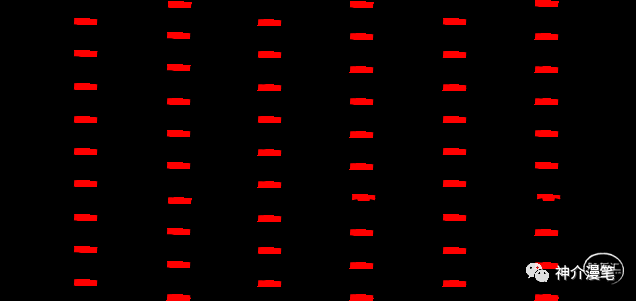

第一个概念:开环支架与闭环支架。开环支架有自己独立的支架单元,每个单元之间有少数几个连接点相连,这样能保证每一个支架单元的相对独立性。在弯曲迂曲,管径差异较大的血管条件下能保持更好的贴壁性。下图即为典型的开环支架设计,红色部分为支架单元之间的连接点,其余部分呈现为开放不连续状态。

闭环支架的设计特点和开环支架刚好相反,所有的支架单元都呈现出连续封闭的状态,整个支架为一个连续完成的整体。其设计的特点使得其网眼更小,更利于提高局部金属覆盖率与对斑块的保护。但是其在迂曲血管的贴壁性会略差,同时因为其作为一个整体存在的特点,其趋势是使血管变直。因此对于血管走形的改变会略大。下图为闭环支架的设计特点,可以看到所有支架网格均为封闭连续的结构。

编织支架在不同管腔内会拉伸,并有释放后短缩现象。雕刻支架:金属圆筒由激光镂空雕刻形成,雕刻支架长度基本稳定,拉伸或短缩的现象极为少见。从结构特点上我们能知道,开环支架全部是雕刻支架,闭环则可能是雕刻也可能是编织。看过我这篇小豆腐块的同志,千万不要再从你们嘴里出现编织开环支架这个词了。下面第一个图,编织闭环支架,第二图为激光雕刻开环支架。